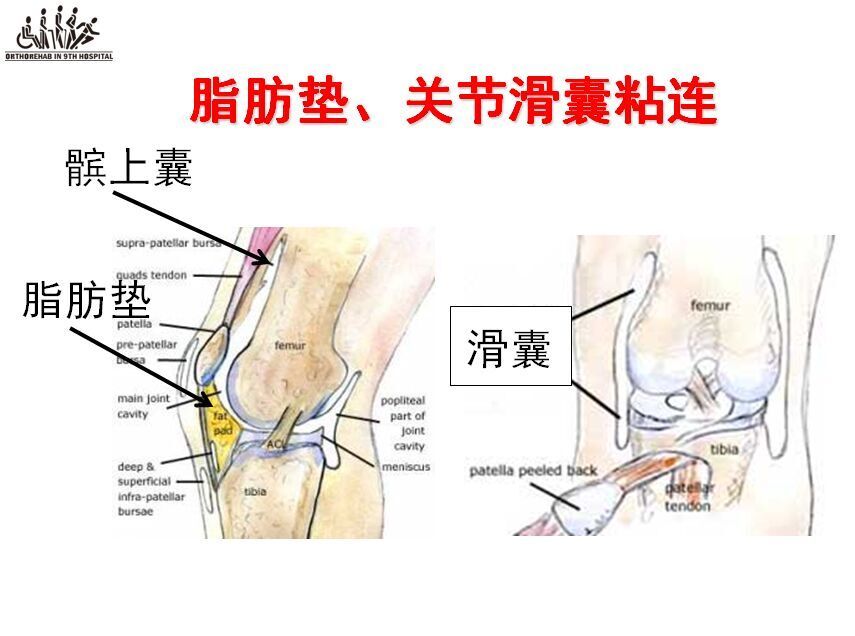

Acl再建術後の留意点 1 再断裂やゆるみの可能性について 2 術後の靭帯は、手術直後から3~4ヶ月程度はかなり弱いため、無理な運動や過度の力がかか れば伸びたり、切れてしまう可能性があります。Acl術後では、方向転換・ジャンプ・着地・カッティング・減速動作など、acl損傷の受傷機転になりうる動作の獲得が最も難しいと言われています。 これらは 損傷した膝の不安定性や筋力の回復の程度が動作に影響します 。• ACL 損傷は、頻度の高い膝関節外傷であり、 損傷によりスポーツ活動が著しく制限される • ACL再建術後の合併症のうち、伸展制限は 重要なものの1つである Gobbi et al Clin Orth 12 Hamidreza Y J Ortho Traum16